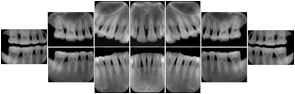

OO.1.2 Ophthalmology

1. A patient in rural Canada visits a general ophthalmologist and is found to have diabetic macular edema. The general ophthalmologist would like to discuss the case with a retina specialist before performing laser surgery. A fluorescein angiogram is done with multiple retinal images taken in a timed series after an intravenous injection. The images along with a Structured Display are shared via a Health Information Exchange with a retina specialist in Calgary, who opens them using his Ophthalmology EMR software and consults via phone with the general ophthalmologist. Both physicians view the images in the same layout so the retina specialist can provide accurate guidance for treating the patient.

2. A patient in rural Iowa visits his primary care physician for management of diabetes. Three non-mydriatic (patient's eyes are not dilated) photographs are taken of the back of each eye, and forwarded electronically along with a Structured Display to an ophthalmologist in Iowa City. The ophthalmologist reads the photos in an agreed upon layout so there is no mistake about what portion of which eye is being viewed. The ophthalmologist is able to tell the primary care physician that his patient does not need to come to Iowa City for face to face ophthalmologic care, but that there is a particular view of the left eye that should be photographed again in 6 months.

Ophthalmic Retinal Study Structured Display

Figure OO-3. Ophthalmic Retinal Study Structured Display